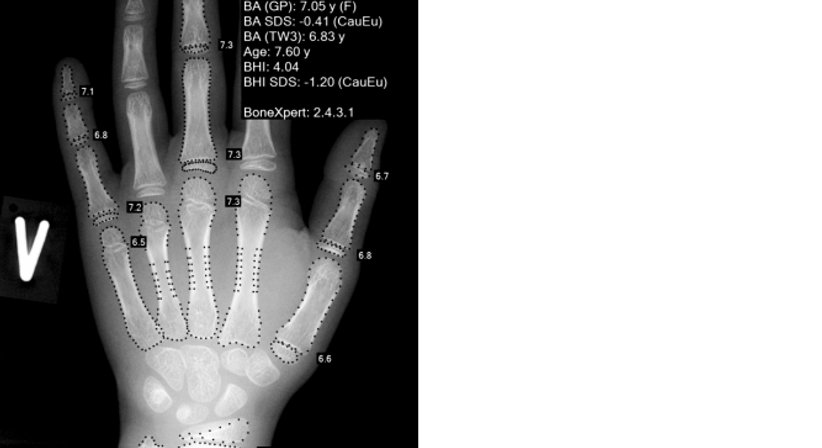

Mit einem Handröntgen und dem Analyseprogramm BoneXpert können wir die zu erwartende Wachstums-Endgröße bestimmen.

Die Programm wertet die Skelettreifung aus und berechnet mit der aktuellen Größe die zu erwartende Größe nach Abschluss des Knochenwachstums.